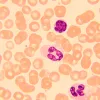

The MAGUS Bio D250T biological microscope is a professional instrument for observing biological specimens in transmitted light. The primary observation technique is a brightfield technique (ready-to-use). Darkfield, polarization, and phase contrast techniques are also available, but they require additional microscope accessories. The microscope is excellent for laboratory and research observations in medicine, pharmaceuticals, forensics, agriculture, and other fields.

Digital camera

The MAGUS CDF50 digital camera is designed for the brightfield microscopy technique. It offers a low noise level and high light sensitivity.

The camera is equipped with a 2.1MP sensor and delivers realistic Full HD images (1920x1080px) when observing with 40x, 60x, and 100x objectives.

Video is recorded at 96fps at maximum resolution: It is smooth, with soft and subtle transitions between frames. The movement of the sample is displayed in real time with no delays. The camera makes it easy to work with moving objects and is suitable for classroom demonstrations.

The camera is equipped with a USB3.0 interface. The data transfer speed is 10 times faster than USB2.0 cameras. The high-speed camera is recommended for professional laboratories, research, or university training.

- For brightfield and darkfield microscopy with 40x, 60x, and 100x objectives; large pixel camera with 8935mV light sensitivity with 1/30s for darkfield microscopy observations at high magnification

- SONY Exmor backlit color CMOS sensor provides low noise level and high light sensitivity even in low-light conditions. You will get clearer, brighter, and more color-saturated images